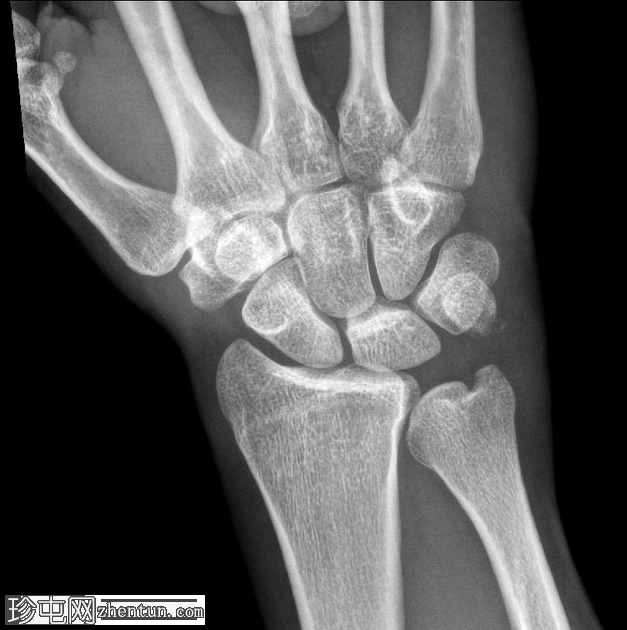

X线片

正位片

可见豌豆骨皮质明显中断,并伴有一小块邻近骨碎片,符合皮质骨折的表现。此外,其上方软组织肿胀,提示急性骨折。

尺骨茎突可见透亮区,符合无移位尺骨茎突骨折的表现。